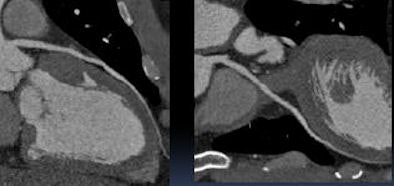

![]() |

| A 44-year-old man with atypical chest pain and a family history of coronary artery disease. Far left, 320-slice coronary CT angiography was performed from the emergency department. Patient has mild mixed plaque in the right coronary artery. Right, same patient showing mild noncalcified plaque in the left anterior descending artery. |